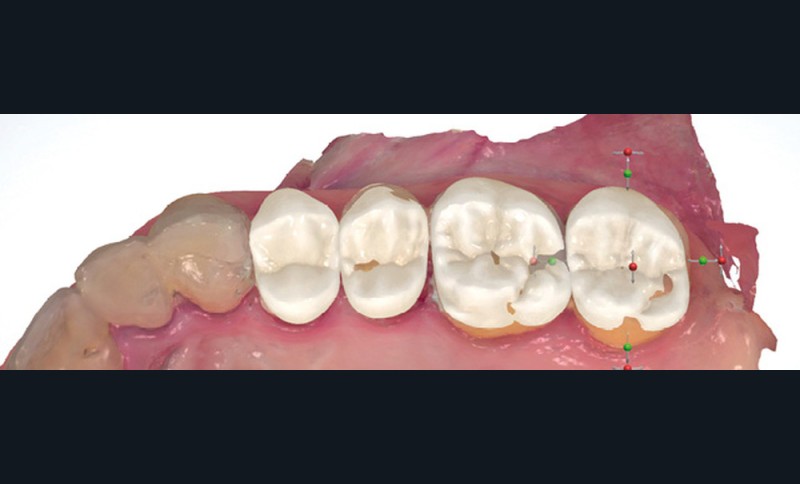

Enfin, des outils d’analyse sont de plus en plus présents avec les systèmes d’empreinte, notamment pour analyser les épaisseurs préparées (avec des outils de coupe) ou pour étudier le parallélisme entre des dents dans les cas de bridge (fig. 2).

Lors de la préparation de piliers de bridge, la difficulté principale est de réussir à paralléliser correctement les piliers pour trouver un axe d’insertion pour la future prothèse. Là encore, l’empreinte optique facilite l’évaluation du parallélisme avec des outils très visuels et simples d’utilisation (fig. 8).